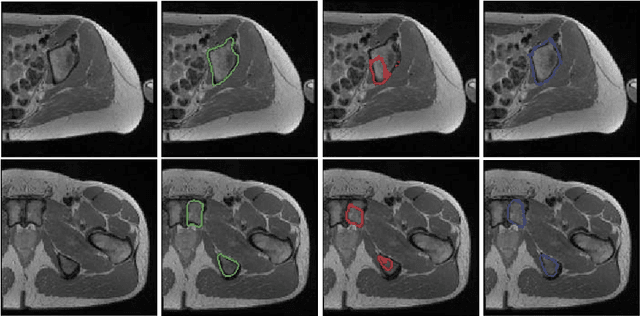

Abstract:Segmentation of abdominal organs has been a comprehensive, yet unresolved, research field for many years. In the last decade, intensive developments in deep learning (DL) have introduced new state-of-the-art segmentation systems. Despite outperforming the overall accuracy of existing systems, the effects of DL model properties and parameters on the performance is hard to interpret. This makes comparative analysis a necessary tool to achieve explainable studies and systems. Moreover, the performance of DL for emerging learning approaches such as cross-modality and multi-modal tasks have been rarely discussed. In order to expand the knowledge in these topics, CHAOS -- Combined (CT-MR) Healthy Abdominal Organ Segmentation challenge has been organized in the IEEE International Symposium on Biomedical Imaging (ISBI), 2019, in Venice, Italy. Despite a large number of the previous abdomen related challenges, the majority of which are focused on tumor/lesion detection and/or classification with a single modality, CHAOS provides both abdominal CT and MR data from healthy subjects. Five different and complementary tasks have been designed to analyze the capabilities of the current approaches from multiple perspectives. The results are investigated thoroughly, compared with manual annotations and interactive methods. The outcomes are reported in detail to reflect the latest advancements in the field. CHAOS challenge and data will be available online to provide a continuous benchmark resource for segmentation.

Abstract:We propose a 2D Encoder-Decoder based deep learning architecture for semantic segmentation, that incorporates anatomical priors by imitating the encoder component of an autoencoder in latent space. The autoencoder is additionally enhanced by means of hierarchical features, extracted by an U-Net module. Our suggested architecture is trained in an end-to-end manner and is evaluated on the example of pelvic bone segmentation in MRI. A comparison to the standard U-Net architecture shows promising improvements.